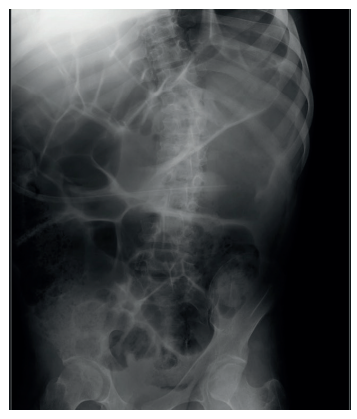

Las manifestaciones óseas son características en los distintos tipos de MPS. En el caso de la MPS III las manifestaciones son menos prevalentes y de menor gravedad, necesitando rara vez de intervención quirúrgica.

A nivel de miembros superiores se observa también en el síndrome de Sanfilippo una mayor incidencia de túnel carpiano. En la columna se puede observar escoliosis, aunque más leve que en otras MPS, hipoplasia de cuerpos vertebrales, pero no las alteraciones a nivel cervical que se observan en los otros grupos de MPS. Es bastante frecuente también el hallazgo de osteonecrosis de cadera. Las contracturas son frecuentes en dicho síndrome, llegando a limitar la movilidad de los pacientes. Las alteraciones del crecimiento se dan sólo en el 50% de pacientes mayores a los 12 años17.